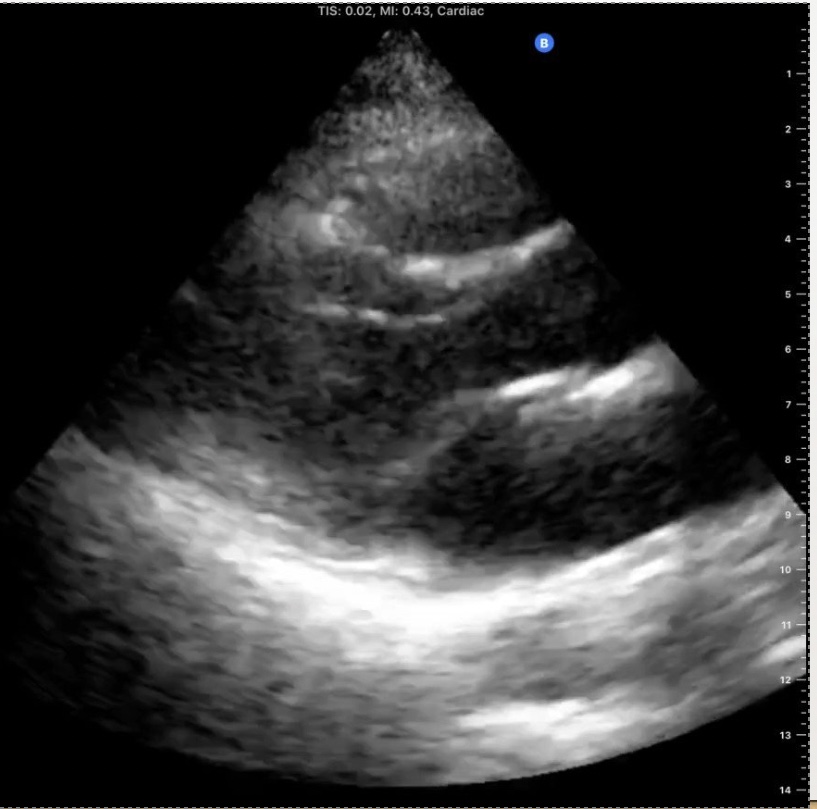

What view is this?

Parasternal long axis (PLAX)

Identify the view and the structures on this echo